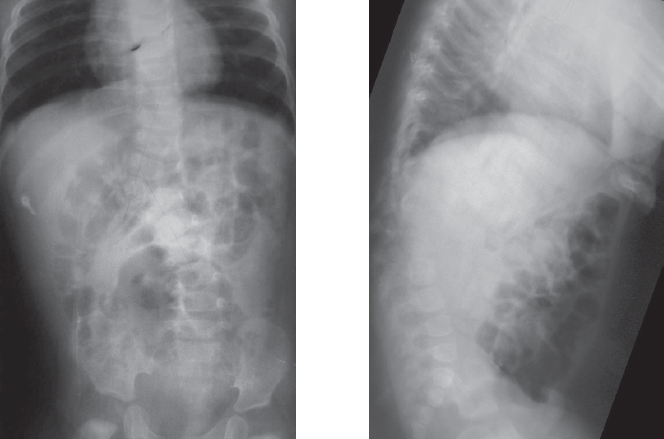

Наложено краниофеморальное скелетное вытяжение. За 35 суток достигнута коррекция сколиотической деформации на 17° (32 %), кифотической — на 12° (14 %). Учитывая расположение правого мочеточника в зоне доступа к телам позвонков грудопоясничного перехода, непосредственно перед основным этапом оперативного лечения под контролем флюороскопии в мочеточник заведен стент. В положении на левом боку выполнена торакофренолюмботомия через ложе 12-го ребра. Отмечено снижение высоты межпозвонковых дисков, отсутствие пульпозных ядер на вершине деформации, конкресценция тел Th12 и полупозвонка L1. Дискэпифизэктомия в парах Th11-Th12, L1-L2, L2-L3, спондилодез сульфатом кальция в комбинации с аутогенной костью (резецированное ребро). Между телами позвонков Th11 и L3 установлен сетчатый имплант Mash. Через тела позвонков Th11 и L3 бикортикально проведены винты, коммутированы стержнем. Плевральная полость и забрюшинное пространство дренированы. Рана послойно ушита. На 12-е сутки после операции больная вертикализирована в корсете. Через 5 месяцев госпитализирована для контрольного обследования и проведения заключительного этапа хирургического лечения. По данным рентгенографии, достигнутая коррекция сохраняется (рис. 5). В качестве заключительной операции выполнен задний спондилодез на вершине деформации.

Рис. 5. Рентгенограммы через 5 месяцев после операции